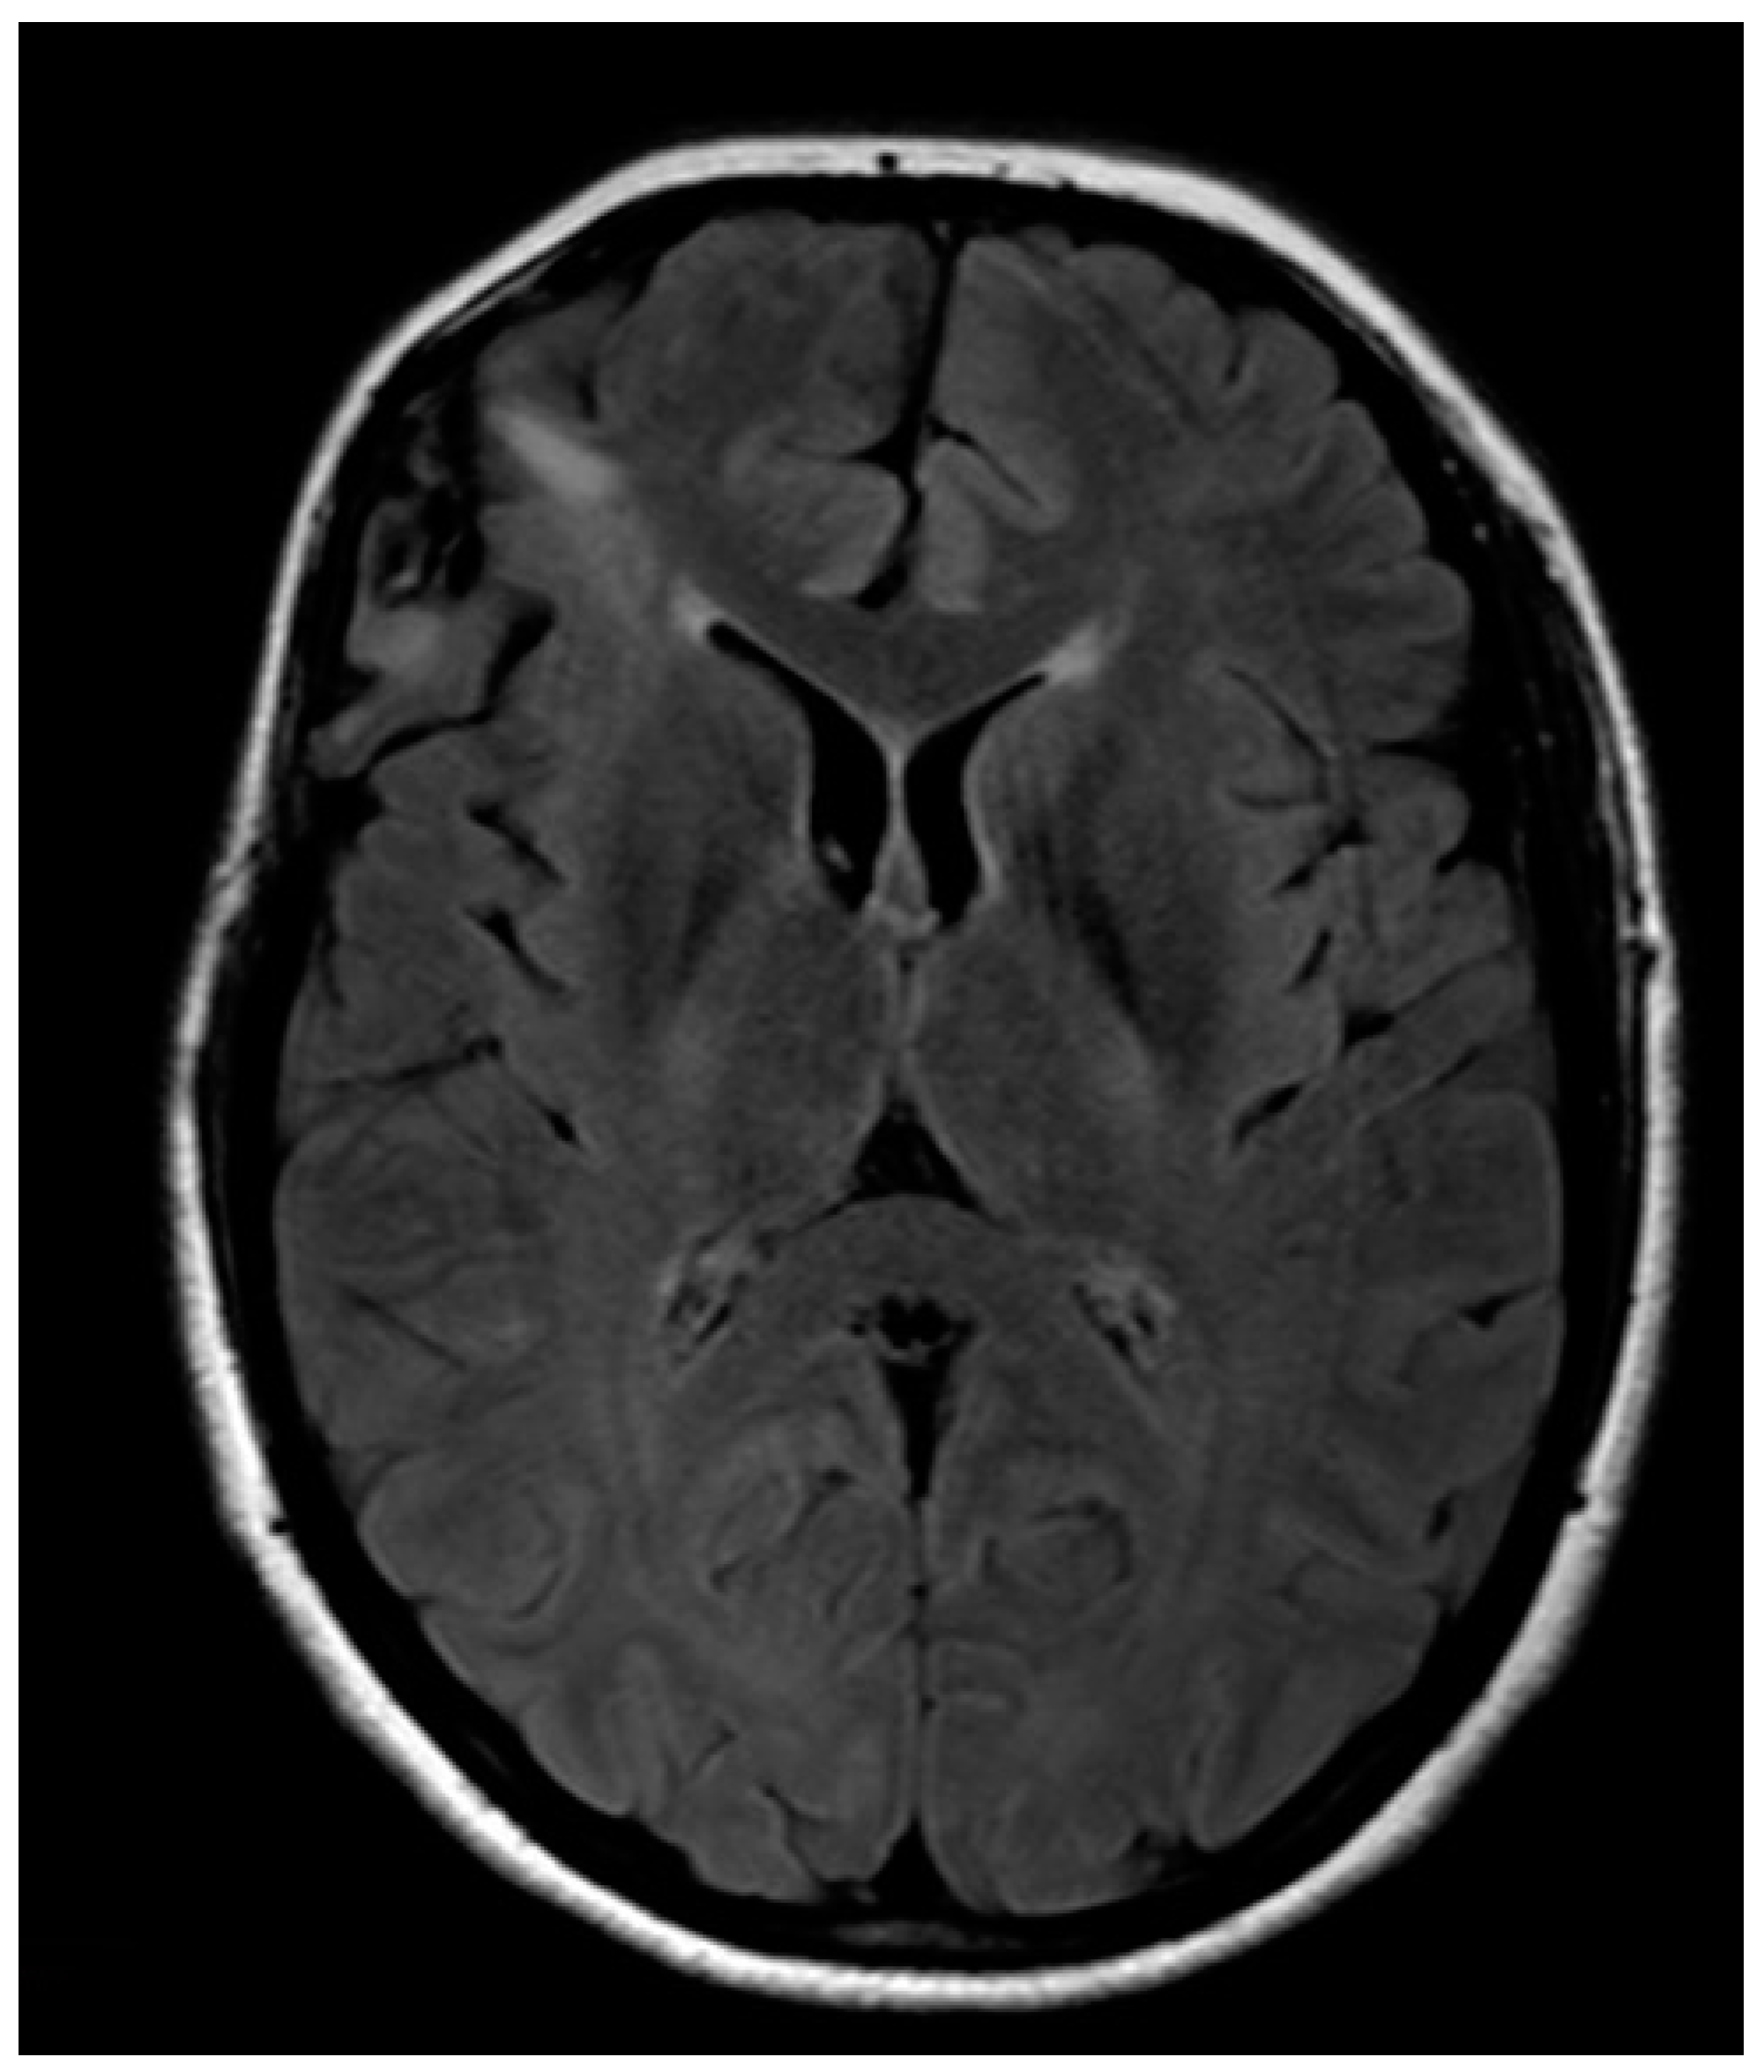

A 32-year-old left-handed female patient was referred to our department with an MR scan showing a right fronto-opercular diffuse low-grade glioma and performed as a diagnostic work-up for headache (Figure 1). Left-handedness was confirmed with Edinburgh’s inventory. She had no preoperative language disorders.

Figure 1. Anatomical MRI scan showing right fronto-opercular diffuse low-grade glioma.

Brainsci 08 00192 g001